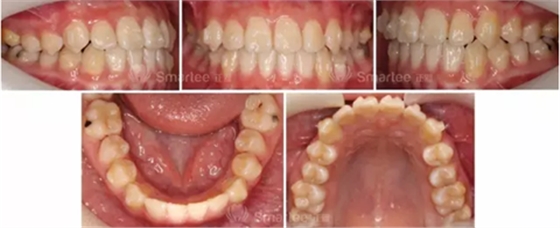

(矯治2個月)

(矯治5個月)